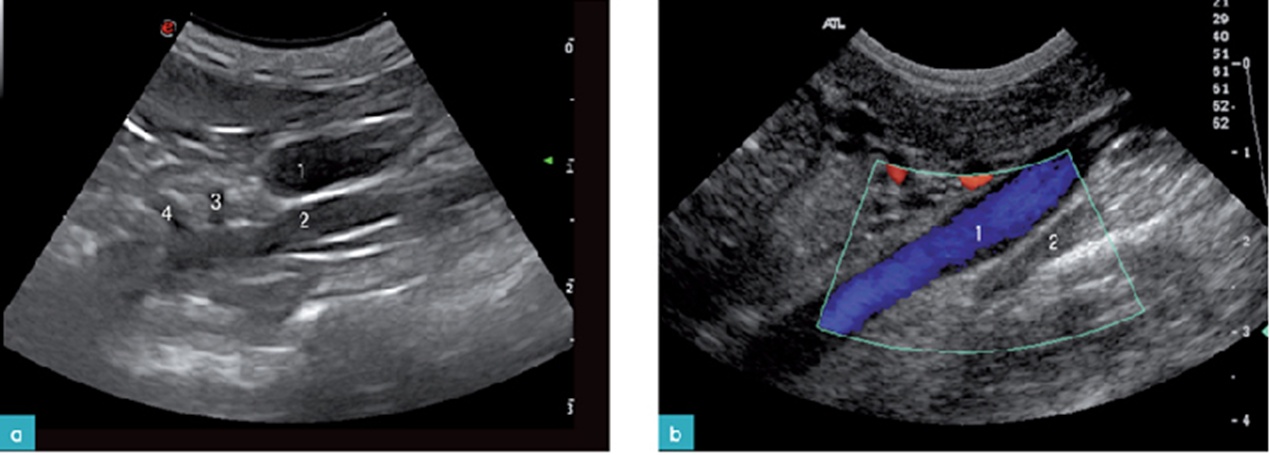

데일리벳 커뮤니티에서 좌측 부신은 환자를 dorsal recumbency나 우측 외측상으로 눕힌 뒤, 좌측 신장의 앞부분을 찾습니다. 이 지점에서 프로브를 내측으로 이동하여 시상면의 복강 대동맥을 위치한 뒤, 신장 동맥을 찾습니다. 신장 동맥을 찾은 뒤에 프로브를 동맥의 앞쪽 부분으로 약간 전진하여, 전장간막 동맥(cranial mesenteric artery)을 찾으면, 이 동맥 바로 뒤에 좌측 부신이 있습니다.

우측 데일리벳 커뮤니티을 검사하기 위해서는 환자를 dorsal recumbency나 좌측 외측상으로 눕힌 뒤, 프로브를 늑골궁 뒤에 위치시킵니다. 우측 신장의 바로 앞쪽에 있는 후대정맥(CVC; caudal vena cava)을 해부학적으로 찾는 위치(이정표)로 참고 하는데, 이는 우측 데일리벳 커뮤니티이 후대정맥의 배외측(dorsolateral)에 존재하고 있기 때문입니다. 특히 우측 데일리벳 커뮤니티을 찾기 어려운 것은 간의 바로 뒤쪽 부분의 후대정맥 근처에서 발견되고, 우측 신장의 앞내측 혹은 안쪽의 위치와 후대정맥의 등외측에서 보이기 때문입니다.(7)

이때 보이는 데일리벳 커뮤니티의 모양은 개와 달리 난원형(oval shape)이나 개에서와 비슷한 두 개의 엽 모양(bilobed shape)으로 보이며, 실질은 저에코성으로 보입니다.